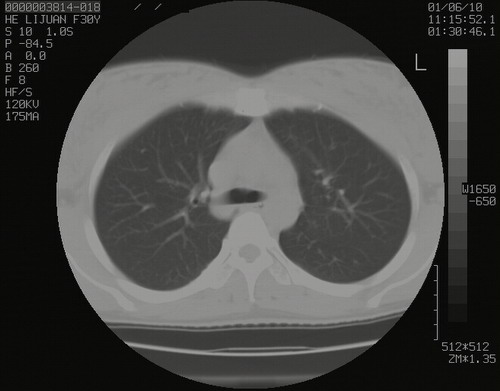

怀孕3个月时(2009-3至4月间),自述突感左侧前后胸疼痛1天,以前胸明显,随后偶感闷痛,余未见异

左肺尖脊柱旁沟肿块,境界清楚,边缘光滑,密度不均,内有多发点片状钙化,考虑良性肿瘤,骨软骨瘤或神经源性肿瘤可能,肺错构瘤不除外。

左后上纵隔见一类圆形肿块影,外侧边界清,密度不均匀,内可见点状钙化影,增强呈不均匀强化,考虑神经源性肿瘤可能。期待病理结果。